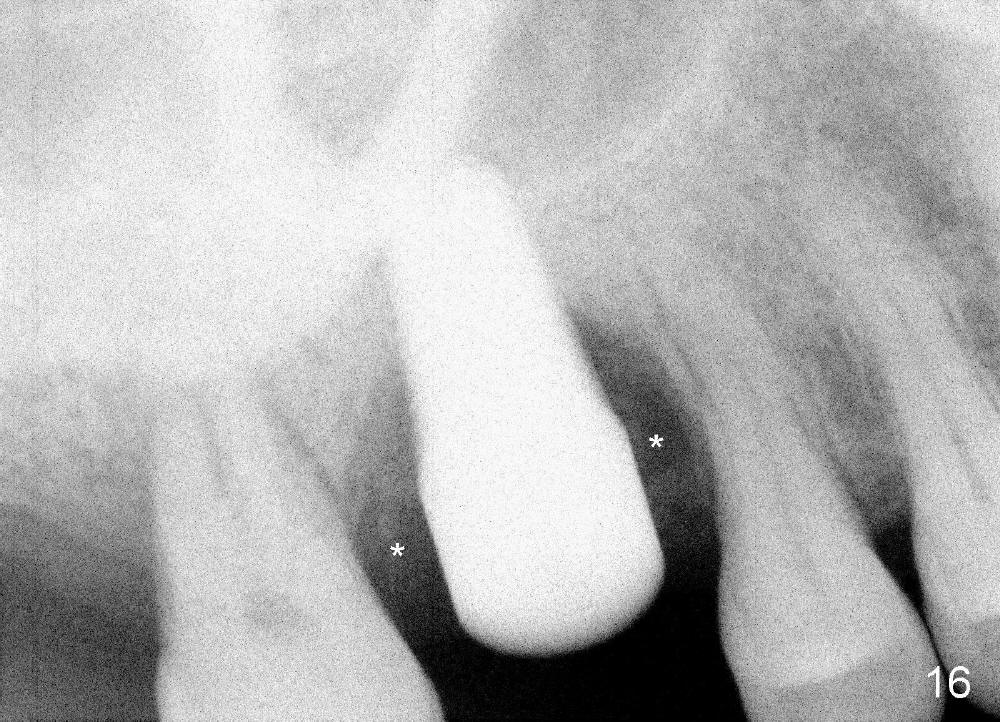

The upper right 1st molar of a 48-year-old man has severe perio endo disease (Fig.1 #3); the bone height for immediate implant (Fig.2) is about 3.5 mm (Fig.1 vertical line). There is a buccal (Fig.3 B) abscess (*); the palatal (Fig.4 P) root is exposed. After extraction, the socket available for immediate implant (Fig.5,6 S) is buccal (without septum), whereas the apex of the palatal root is far away from the main socket. In fact there is an advantage: the socket is smaller. Osteotomy is created in the main socket as palatal as possible, using osteotomes, reamers and taps (Fig.7 T). The sinus floor is lifted (Fig.7 ^). When 7x17 mm implant is placed (Fig.8 I), the insertion torque is >60 Ncm. The remaining socket (Fig.8 *) is to be packed with mixture of autogenous bone, allograft and synthetic bone (Osteogen) (Fig.9,10 <). Immediate insertion of an abutment (Fig.8-10 A) helps retain perio dressing (Fig.11,12). No collagen membrane is used in this case to cover the bone graft before placement of perio dressing. Postop the patient cannot tolerate oral Amoxicillin because of stomach upset. The dose is reduced. Two weeks postop, the perio dressing is stable, but discolors (Fig.13). When the dressing is removed, the buccal bone graft is exposed, which is not abnormal. What is unusual is discoloration (Fig.14). The significance of the latter is not revealed until 3 months postop when the patient remains asymptomatic, but there is an apical fistula (Fig.15 <). There is a communication between the fistula and the buccal sulcus of the implant: water passing freely. Based on the position of the buccal plate of the neighboring teeth (*), the buccal plate of the implant should be lost, which is consistent with finding of PA (Fig.16, as compared to Fig.8). Guided bone regeneration seems necessary.